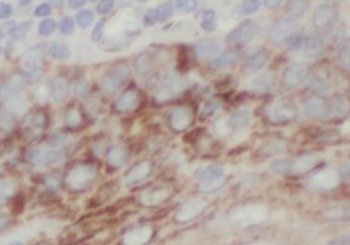

| 验证图片 | Immunohistochemistry of paraffin-embedded human skin using FNab03670(GSDMD antibody) at dilution of 1:50 Jurkat cells were subjected to SDS PAGE followed by western blot with FNab03670(GSDMD Antibody) at dilution of 1:500 |